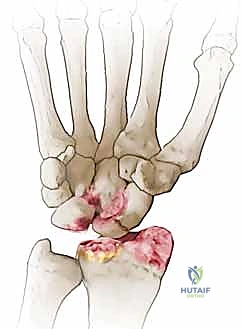

- المرحلة الأولى (Stage I): خشونة وتآكل في المفصل بين القطب البعيد للعظم الزورقي وعظم الكعبرة (الناتئ الإبري الكعبري).

- المرحلة الثانية (Stage II): يمتد التآكل والخشونة ليشمل المفصل الزورقي الكبير (Scaphocapitate joint).

- المرحلة الثالثة (Stage III): تدهور كامل يشمل المفصل بين عظم الهلالي والعظم الكبير (Capitolunate joint)، مع انهيار كامل لهيكل الرسغ.

تُعد عملية استئصال القطب البعيد للعظم الزورقي (Excision of the Distal Pole of the Scaphoid) حلاً جراحياً ذكياً ومبتكراً. الفكرة الميكانيكية وراء هذه الجراحة هي: "إذا كان القطب البعيد للعظم الزورقي هو الذي يحتك بعظم الكعبرة ويسبب الألم والخشونة، فلنقم بإزالته مع الحفاظ على باقي هياكل الرسغ".

في حال كانت الخشونة قد وصلت لمراحل متقدمة جداً (المرحلة الثالثة)، فإن استئصال القطب البعيد قد لا يكون كافياً. هنا تبرز خبرة البروفيسور هطيف في تقديم البدائل الجراحية المعقدة: